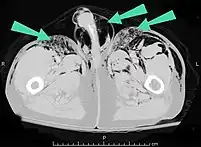

Air can be trapped under the skin in necrotizing infections such as gangrene, occurring as a late sign in gas gangrene,[2] of which it is the hallmark sign. Subcutaneous emphysema is also considered a hallmark of Fournier gangrene.[26] Symptoms of subcutaneous emphysema can result when infectious organisms produce gas by fermentation. When emphysema occurs due to infection, signs that the infection is systemic (i.e. that it has spread beyond the initial location) are also present.[9][21]

Significant cases of subcutaneous emphysema are easy to diagnose because of the characteristic signs of the condition.[1] In some cases, the signs are subtle, making diagnosis more difficult.[13] Medical imaging is used to diagnose the condition or confirm a diagnosis made using clinical signs. On a chest radiograph, subcutaneous emphysema may be seen as radiolucent striations in the pattern expected from the pectoralis major muscle group. Air in the subcutaneous tissues may interfere with radiography of the chest, potentially obscuring serious conditions such as pneumothorax.[18] It can also reduce the effectiveness of chest ultrasound.[27] On the other hand, since subcutaneous emphysema may become apparent in chest X-rays before a pneumothorax does, its presence may be used to infer that of the latter injury.[13] Subcutaneous emphysema can also be seen in CT scans, with the air pockets appearing as dark areas. CT scanning is so sensitive that it commonly makes it possible to find the exact spot from which air is entering the soft tissues.[13] In 1944, M.T. Macklin and C.C. Macklin published further insights into the pathophysiology of spontaneous Macklin's Syndrome occurring as a result of a severe asthmatic attack.